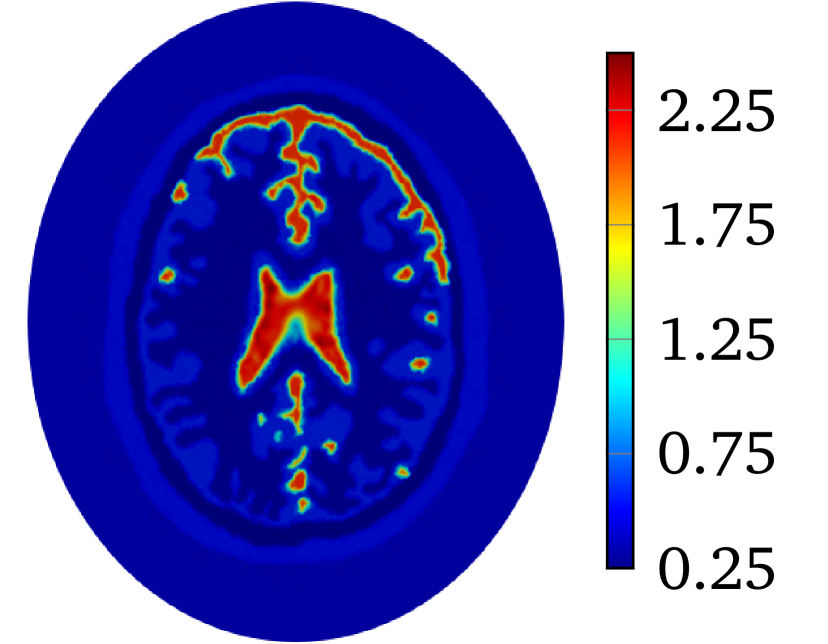

Though LM-SCEM performs well for reconstructing the conductivity map, its efficiency of the computation decreases quickly with the increase of measurements. Since EIT is not very sensitive to the change of interior conductivity, the electrical potential should converge faster than the convergence of the conductivity. The human-brain model is used here for numerical experiments with LM-SCEM. The elliptic domain is characterized with 8 cmtimes8cm8\text{\,}\mathrm{c}\mathrm{m} major and 9 cmtimes9cm9\text{\,}\mathrm{c}\mathrm{m} minor axes, and the domain is meshed with 36893 triangular elements. The parameters are given as α0=150subscript𝛼0150\alpha_{0}=150, a=2.0𝑎2.0a=2.0 and β=1×103𝛽1E-3\beta=$1\text{\times}{10}^{-3}$. The current patterns I(2)superscript𝐼2I^{(2)} and I(3)superscript𝐼3I^{(3)} are used in the reconstruction. With 60 dBtimes60dB60\text{\,}\mathrm{d}\mathrm{B} noise, the iteration is terminated when τL2<1×104subscriptnorm𝜏superscript𝐿21E-4\|\tau\|_{L^{2}}<$1\text{\times}{10}^{-4}$ or the maximum number of iterations equals 30. The reconstruction based on LM-SCEM is shown in Figure 7(a). 𝒰superscript𝒰\mathbfcal{U}^{k} of each current pattern is computed with SCEM and σksubscript𝜎𝑘\sigma_{k} for k𝑘k-th iteration, ηbsuperscript𝜂𝑏\eta^{b} easily follows then. The variation of the relative error η𝜂\eta and ηbsuperscript𝜂𝑏\eta^{b} are shown in Figure 6(a) and Figure 6(b), respectively. As can be seen, η𝜂\eta slowly converges to 4.09%percent4.094.09\%. This error is much larger than the input noise level, this is mainly caused by the complexity of the phantom and the high contrast of σ𝜎\sigma among different tissues. But the potentials on the boundary for both I(2)superscript𝐼2I^{(2)} and I(3)superscript𝐼3I^{(3)} converge fast to a level of ηb<1×104superscript𝜂𝑏1E-4\eta^{b}<$1\text{\times}{10}^{-4}$ in few iterations. Therefore, the boundary potential converges much faster. This property is exploited here to accelerate the computation by mixing LM-SCEM and LM-DCM, as demonstrated in Algorithm 2. In this computation, the LM-SCEM is stoped when ηbsuperscript𝜂𝑏\eta^{b} for all current patterns are smaller than 1×1031E-31\text{\times}{10}^{-3}. The LM-DCM is performed in the region Ω={x|xΩ,dist(x,Ω)>5 mm}superscriptΩconditional-set𝑥formulae-sequence𝑥Ω𝑑𝑖𝑠𝑡𝑥Ωtimes5mm\Omega^{\prime}=\{x\ |\ x\in\Omega,\ dist(x,\partial\Omega)>$5\text{\,}\mathrm{m}\mathrm{m}$\} with δd=5 mmsubscript𝛿𝑑times5mm\delta_{d}=$5\text{\,}\mathrm{m}\mathrm{m}$. The potential on ΩsuperscriptΩ\partial\Omega^{\prime} is computed with SCEM and the reconstructed σ𝜎\sigma from LM-SCEM. The power density in ΩsuperscriptΩ\Omega^{\prime} can be reconstructed with the method introduced by Ammari et al [4]. However, it requires the knowledge on the deformation caused by the ultrasonic waves, therefore, we compute it with DCM instead. Noise with SNR=60 dBabsenttimes60dB=$60\text{\,}\mathrm{d}\mathrm{B}$ is added, and LM-DCM is used for the reconstruction. The relative error η𝜂\eta is given in Figure 6(a). The conductivity map is reconstructed with η=8.13×104𝜂8.13E-4\eta=$8.13\text{\times}{10}^{-4}$ in 30 iterations, and the result is given in Figure 7(b). Here, the time required for 30 LM-DCM iterations is about 20 minutes which is approximately the time needed for one LM-SCEM iteration. So the reconstruction efficiency is greatly improved, and better results are obtained. A similar computation with 40 dBtimes40dB40\text{\,}\mathrm{d}\mathrm{B} noise is further considered here. As seen in Figure 6(b), increasing noise does not influence much the convergence of the boundary potential, therefore, this mixed approach can be a good way to remove noise from the measured power density. With 40dB noise in the reconstructed power density in ΩsuperscriptΩ\Omega^{\prime}, the distribution of σ𝜎\sigma obtained with LM-DCM is shown in Figure 7(d). Comparing it to the results obtained with LM-SCEM, as shown in Figure 7(c), a better noise tolerance is observed in LM-DCM.

Refer to caption

(a) LM-SCEM, SNR = 60 dBtimes60dB60\text{\,}\mathrm{d}\mathrm{B}

(b) Mixed, SNR = 60 dBtimes60dB60\text{\,}\mathrm{d}\mathrm{B}

(c) LM-SCEM, SNR = 40 dBtimes40dB40\text{\,}\mathrm{d}\mathrm{B}

(d) Mixed, SNR = 40 dBtimes40dB40\text{\,}\mathrm{d}\mathrm{B}

Figure 7: The conductivity map of human-brain model reconstructed with current pattern I(2)superscript𝐼2I^{(2)} and I(3)superscript𝐼3I^{(3)}. The reconstruction with only LM-SCEM are given in (a) and (c) for 60 dBtimes60dB60\text{\,}\mathrm{d}\mathrm{B} and 40 dBtimes40dB40\text{\,}\mathrm{d}\mathrm{B} noises. Corresponding reconstructions by mixing LM-SCEM and LM-DCM are given in (b) and (d).